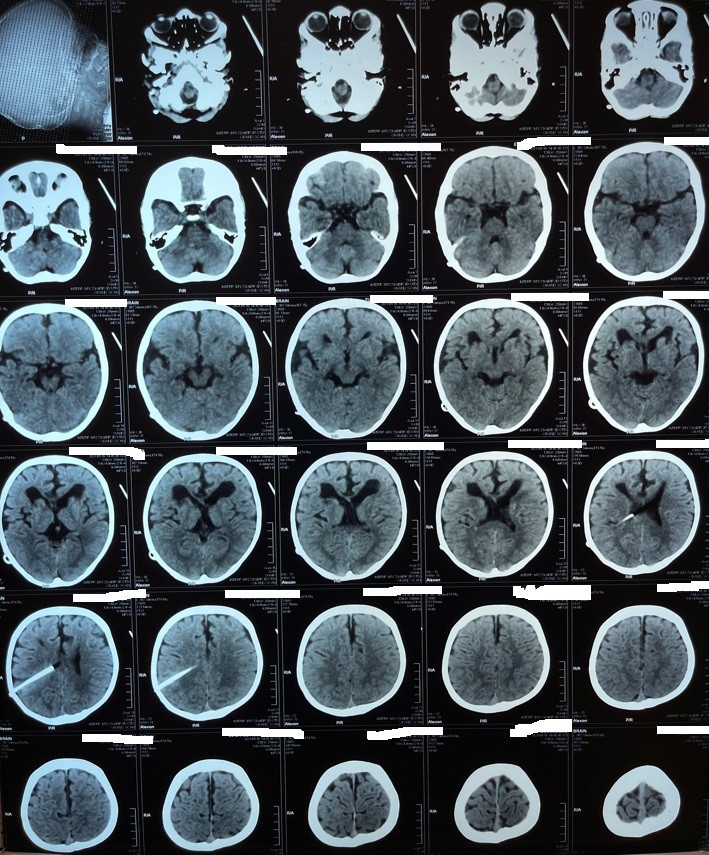

hydrocephalus in a one-year-old child and valve installation